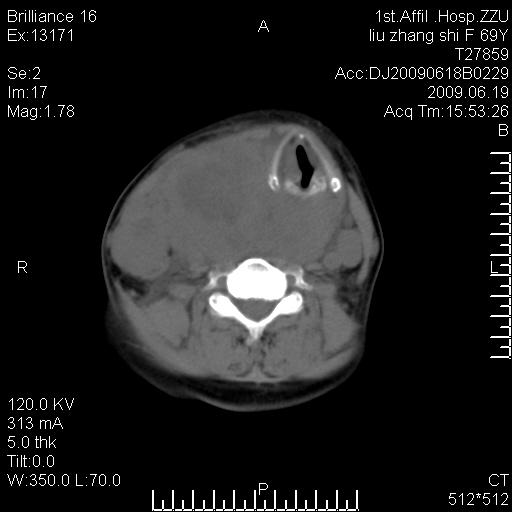

标题: CT26782:女,69岁,颈部占位,3天后公布病理结果。

【病理证实系列】女,69岁,颈部占位,有病理结果,3天后公布。(由于病例时间较久,临床资料不全,请网友见谅)本系列将有几百种常见、少见及罕见病例,均经病理证实。病例资料来自郑州大学第一附属医院。与网友共享,本人有空就发。

甲状腺癌并颈部淋巴结转移。感谢楼主的良苦用心,谢谢。

甲状腺癌并颈部淋巴结转移。

需与鼻咽癌鉴别!

支持甲状腺癌广泛侵及周围结构并颈部淋巴结转移。

鉴别:淋巴瘤、恶性神经源性病变、恶性纤维组织细胞瘤。

病理结果:颈部非霍奇金淋巴瘤。

右侧甲状腺确实有问题